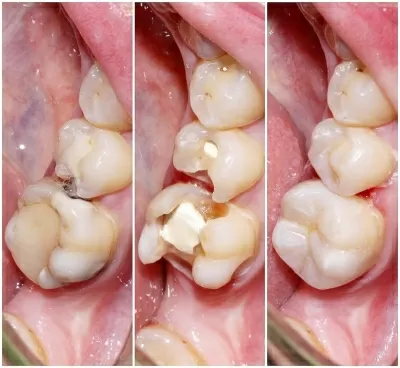

Хочу поблагодарить коллектив стоматологической клиники маэстро!!!Доктора Бардакова Игоря Викторовича и его замечательную команду, за высокий профессионализм чуткость и понимание к своим клиентам!!! Спасибо большое мои дорогие!!! Рекомендую всем кому не безразлична своя улыбка!! Приходите смело в клинику МАЭСТРО не ошибётесь!!!С Уважением Шахова раиса павловна

В стоматологическую клинику МАЭСТРО я пришла по рекомендации.Встретили меня очень тепло.ДОКТОР Игорь Викторович профессионал и умница. Зубы мои стали красивые, а я счастливая.Коллектив у Игоря Викторовича достойный.Как семья.Так приятно.СПАСИБО всему коллективу! Здоровья вам счастья,удачи,мира! Рекомендую всем, кому не все равно как выглядит ваша улыбка и здоровье ваших зубов читать далее